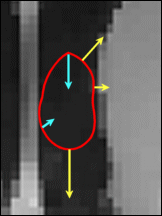

点的速度显示为蓝色和黄色箭头,速度矢量始终指向垂直于蛇的方向。

黄色速度取决于图像特性:在图像强度均匀的地方其强度更强,而在图像强度不均匀、存在边缘的区域其强度较弱

这样就能保证 snake 在图像边缘的扩张速度比在均匀区域的扩张速度慢得多

蓝色速度取决于 snake 的形状:它会在 snake 较弯曲的地方更强,在 snake 较直的地方更弱

这样就能保证其光滑的形状

snake 某点的运动由该点速度矢量之和决定,虚线轮廓表示下一个时间段 snake 的形状。